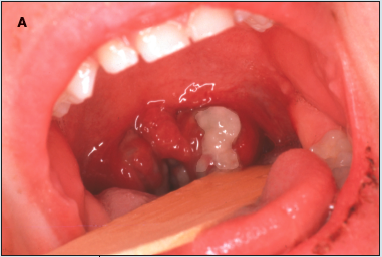

These lesions on the tongue of a 7-year-old white girl had been present since she was 2.